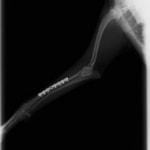

トイプードル 右遠位橈尺骨短斜骨折のALPSによる内固定